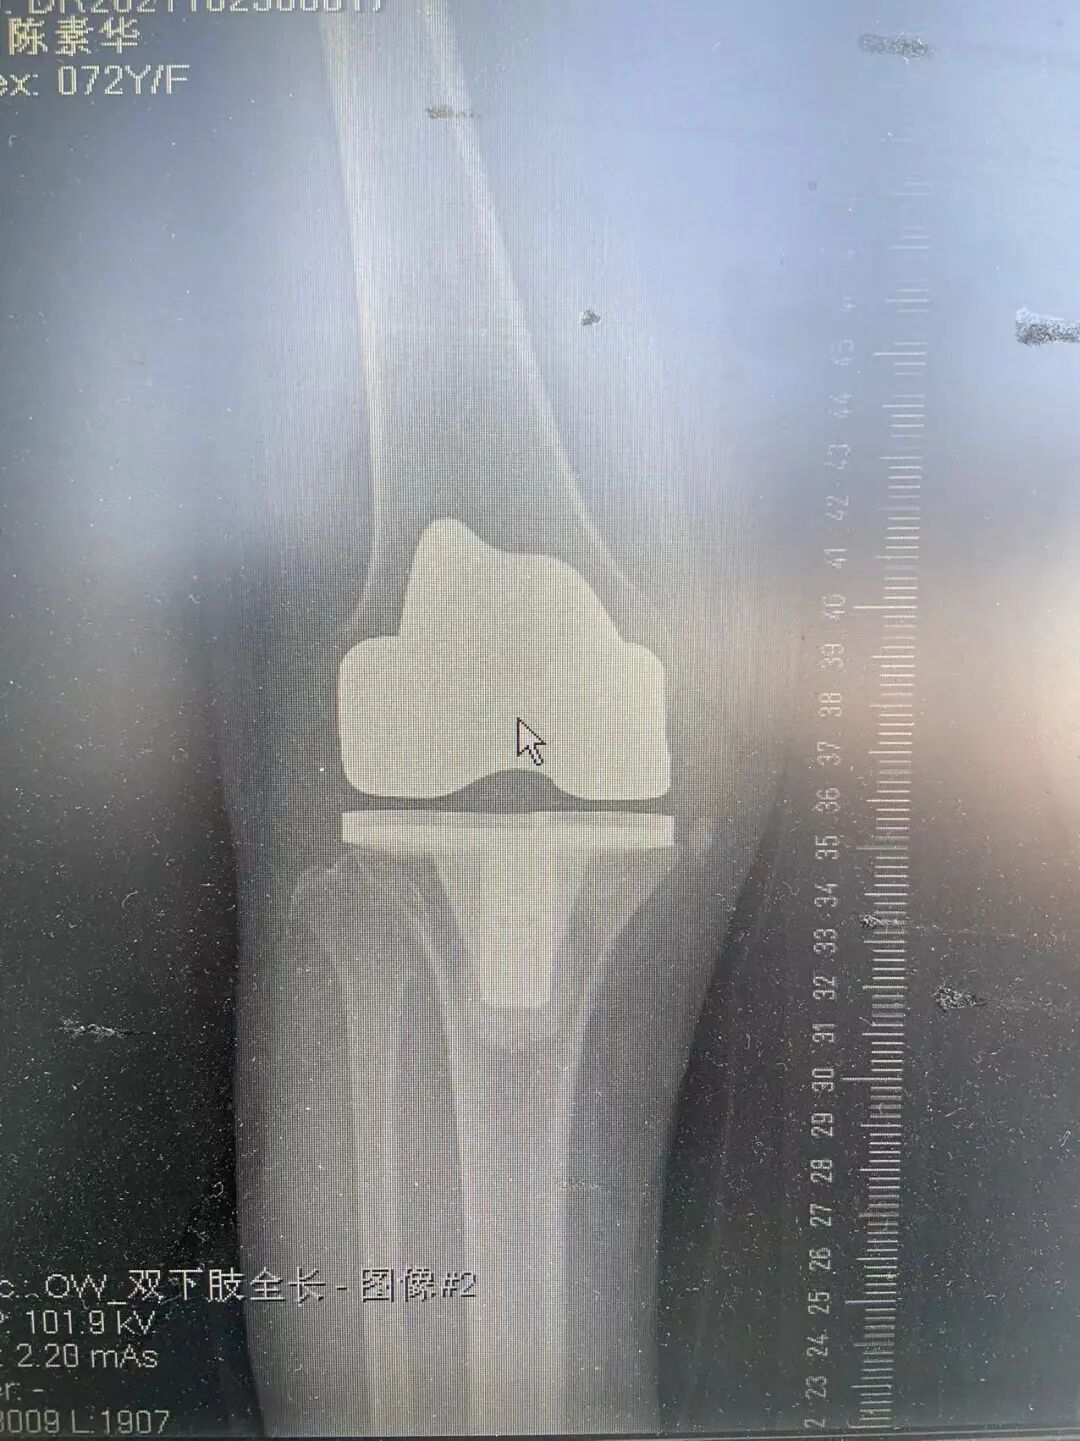

右膝重度骨关节炎

右膝全膝置换术